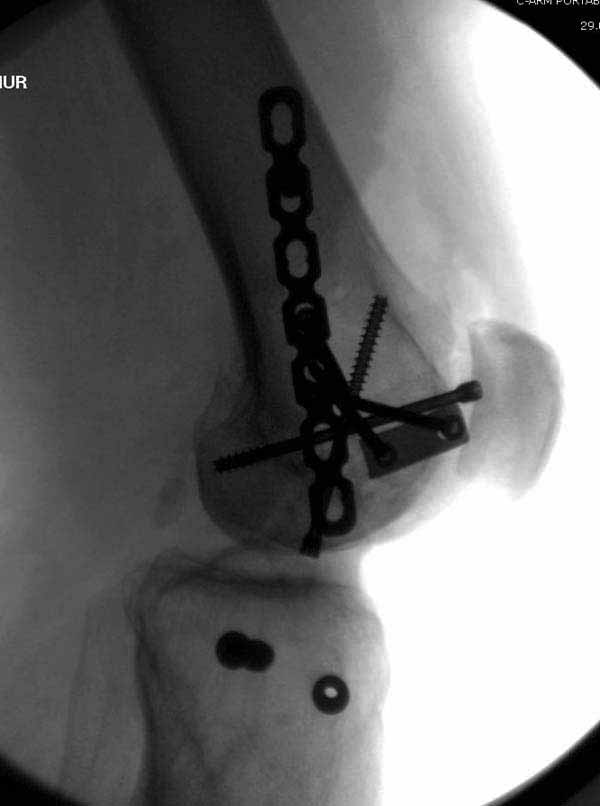

В приложении пример недавней операции, C3, открытая репозиция, фиксация мыщелков спицами и винтами, ретроградный синтез большеберцовым гвоздем 10,5 мм диаметром, винты 5 мм.

Позволю себе напомнить коллегам ещё раз, что являюсь сторонником антеградного остеосинтеза при переломах дистального эпиметафиза бедренной кости. Такая приверженность основана не на преимуществах внесуставного введения стержня или большем проценте положительных результатов. Она основана на возможности обеспечить блокирование на минимальном расстоянии от суставной поверхности в нескомпрометированной кости и, таким образом стабилизировать максимально низкие переломы. В приведенном Вами случае самый дистальный из блокирующих винтов проведен на расстоянии более 2 см от конца стержня. Из-за того, что к стержню присоединяется кондуктор, на стержне теряется 1-1,5 см его длины, где можно было разместить отверстия для блокирования. И что более важно, вместе с потерянной для этой цели длиной стержня утрачивается для размещения блокировочных винтов, пожалуй, самая ценная часть дистального эпиметафиза бедренной кости. Проблемы дистального блокирования в разных плоскостях, локализации точки ввода стержня при антеградном остеосинтезе – это всё решаемые технические проблемы. Но антеградный остеосинтез низких дистальных переломов бедра при адекватном блокировании в нескомпрометированной кости обеспечивает решение стратегической задачи – стабильный остеосинтез и возможность нагрузки.

В приведенном Вами случае самый дистальный из блокирующих винтов проведен на расстоянии более 2 см от конца стержня.

На этом большеберцовом стержне центр ближайшего к кондуктору отверстия в 14 мм от конца. И пример был про то, что пластина тут, скорее всего, была бы не худшим выбором.